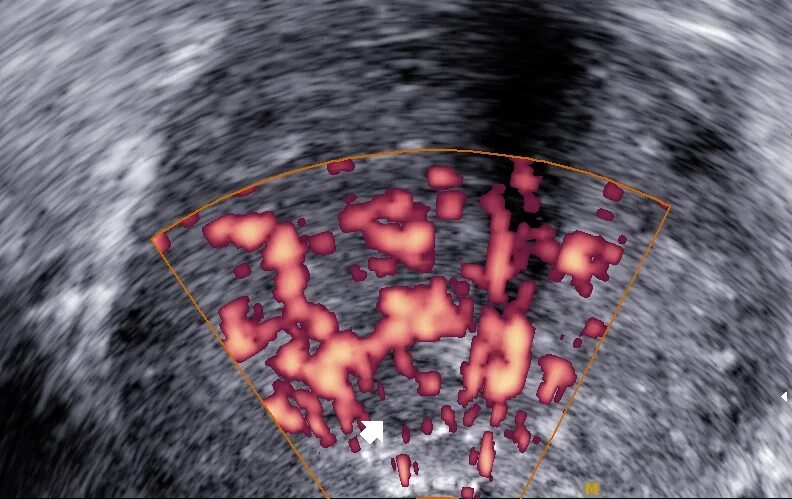

Микрокальцинаты предстательной